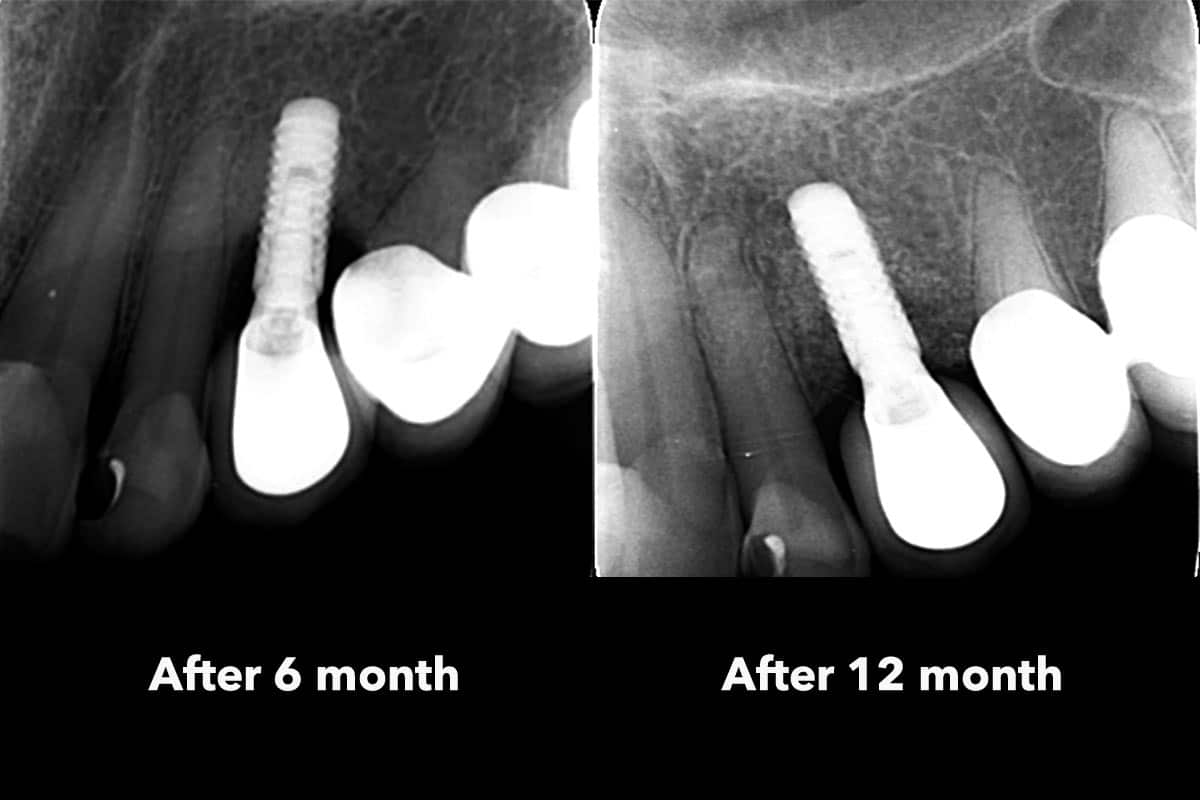

At the 6-month follow-up, clinical and radiographic evaluations demonstrated pronounced new bone formation and favourable soft tissue integration, indicating successful regenerative outcomes. By the 12-month follow-up, bone regeneration had advanced even further, and implant stability was significantly strengthened, confirming the procedure’s lasting success. A CBCT scan at 6 months revealed promising results, which were even more striking at the 12-month mark, demonstrating optimal bone integration and implant stability.